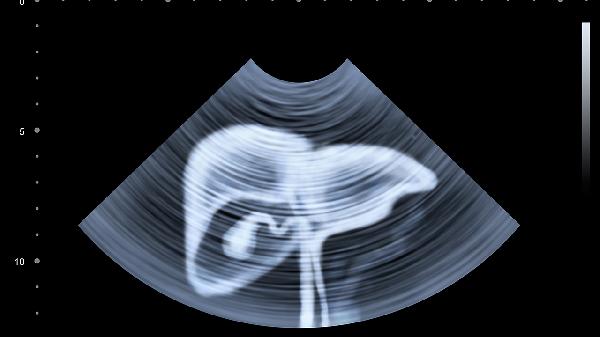

肝脏是体内糖原储存的主要器官,进食后血糖升高时,肝脏将葡萄糖转化为糖原储存;空腹时则分解糖原释放葡萄糖入血。这一动态平衡依赖肝细胞内的糖原合成酶与磷酸化酶活性调节。若肝脏功能受损,可能导致餐后血糖波动加剧或空腹低血糖。

肝脏是胰岛素的主要靶器官,通过抑制糖原分解和糖异生降低血糖;同时响应胰高血糖素促进糖原分解。胰岛素抵抗时,肝脏对胰岛素的敏感性下降,可能导致空腹血糖持续升高,成为2型糖尿病的重要发病机制。

肝脏脂肪堆积(如非酒精性脂肪肝)会干扰胰岛素信号传导,加重胰岛素抵抗。此外,肝脏合成的极低密度脂蛋白增多可能间接影响外周组织对葡萄糖的摄取利用,形成代谢紊乱的恶性循环。

病毒性肝炎、肝硬化等肝脏疾病常伴随糖代谢异常,表现为肝源性糖尿病。这类患者可能出现空腹血糖正常但餐后血糖显著升高的特征,与胰岛β细胞功能受损和肝糖输出增加有关。